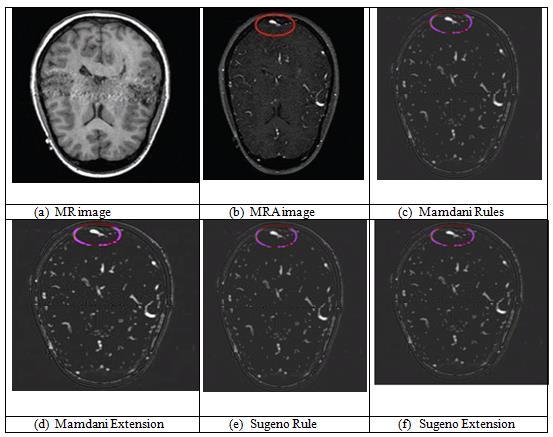

ThefusionfindingsofMRandMRAimagesaredisplayedin Figure4.TheMRinputpictureispicture(a),whiletheMRA input image is Image (b). The fused pictures from the MamdanirulesareshowninImage(c),whilethefusedimages fromtheMamdaniextensionmethodareshowninImage(d). Itisobviousfrompictures(c)and(d)thatthefusedimage producedbyMamdanirulesissubstantiallylessclearthan theonegeneratedbyMamdaniextension.Thefusedimage obtained from the Sugeno extension method is Image (f), while the fused image obtained from the Sugeno rules is

Image(e).Ithasbeendemonstratedbythephotos(e)and(f) that the fused image produced by the Sugeno extension is significantlysuperiortotheoutputimageproducedbythe Sugenorules.

Thetable4aboveliststheobjectivecriteriaforMRandMRA pictures.Here,thequalitymeasurebasedonedges,mutual information,andentropyarecomputed.BothMamdaniand Sugenohavethesameentropyvalues.SugenoFISimprovises Mutual Information values in contrast to Mamdani FIS. MamdaniandSugenorulesbothhavethesameEdgeBased Quality Metric values, yet Mamdani's (QAB/F) values are higherthanSugeno's.